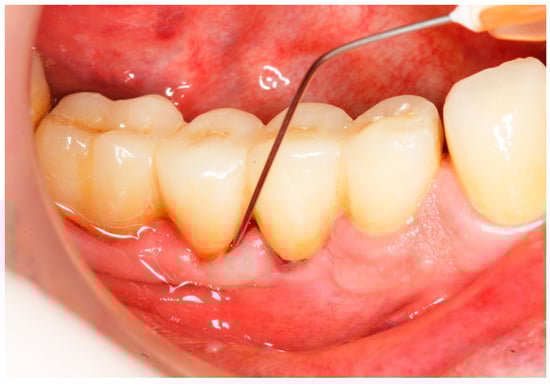

2.6. Clinical Examination

- Implant probing pocket depth (PPD) was measured from the mucosal margin to the bottom of the probable pocket and evaluated at six sites per implant (i.e., disto-buccal, mid-buccal, mesio-buccal, mesio-lingual/palatal, mid-lingual/palatal, disto-lingual/palatal);

2.8. Treatment Procedures

2.9. Evaluation of Treatment Effect